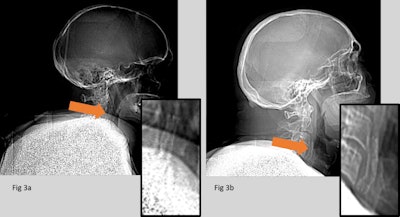

"The presence of two projections, both an anterior-posterior and lateral, helped to localize the position of an implant and to differentiate implants from internal pathology. This informs on the importance of multiple projections in any plain film modality," they explained. "However, some implants were not visible in the images. Both the neurovascular and coronary stents could not be detected as, despite being radiopaque, they are very small and had too fine a mesh to be depicted by this type of imaging."

Similarly, carotid stents or inferior vena cava (IVC) filters, which consist of fine metallic components, although visible, can be partially obscured by anatomy in a crowded projection. Furthermore, as in the case of the missed frenum piercing, rare or unexpected implants might be difficult to find, possibly regardless of the imaging modality, further highlighting the need for specific skills and training, according to the King's College team.